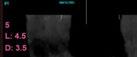

La media de la altura ósea residual en la zona de colocación de los implantes de 4,5 mm fue de 5,20 mm (+/-1). En los implantes insertados se realizaron técnicas accesorias en 12 de los 23 totales. Estas técnicas accesorias fueron elevación de seno transalveolar en seis implantes, sobre-corrección vestibular en cinco implantes y crecimiento vertical en uno de los implantes. El material para todos estos procedimientos fue injerto autólogo obtenido de fresado de otras localizaciones y de la zona de inserción del implante y PRGF-Endoret. En todos los casos se llevó a cabo una carga inmediata de los implantes de 4,5 mm de longitud. De todos los implantes insertados, únicamente dos implantes fueron ferulizados a otros de igual longitud, encontrándose el resto ferulizados a implantes de longitud mayor, formando puentes de entre dos y cuatro dientes en el 69,6% de los casos y de arco completo en el 30,4% restante.

Figuras 13-15. Imágenes del cone-beam de planificación de los cortes mandibulares de los tres implantes de 4,5 mm de longitud. Como podemos observar en los tres casos, la atrofia en altura es muy llamativa, habiéndose necesitado procedimientos regenerativos previos en caso de haber colocado implantes de longitud convencional.